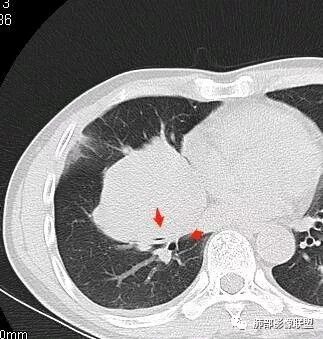

南边:深分叶、大肿块

南边:主体在下叶前基底段

南边:边缘膨隆

南边:中叶、下叶背段支气管推移

南边:中叶支气管腔内似有粘液栓,外侧段有炎性病变

南边:有老师问为啥考虑中叶支气管受压?不是支气管来源的?

1、主体病灶在下叶

2、支气管腔还在,有移位

但是现在的片显示,其主体在下叶,中叶支气管壁由下朝上有推移

南边:下叶的支气管受压后移、变形

南边:病灶边界清,提示侵袭性弱,膨胀生长为主;这时候我们提示病灶不应该是支气管关系密切,提示间叶来源或胸膜来源

深分叶,警惕恶性